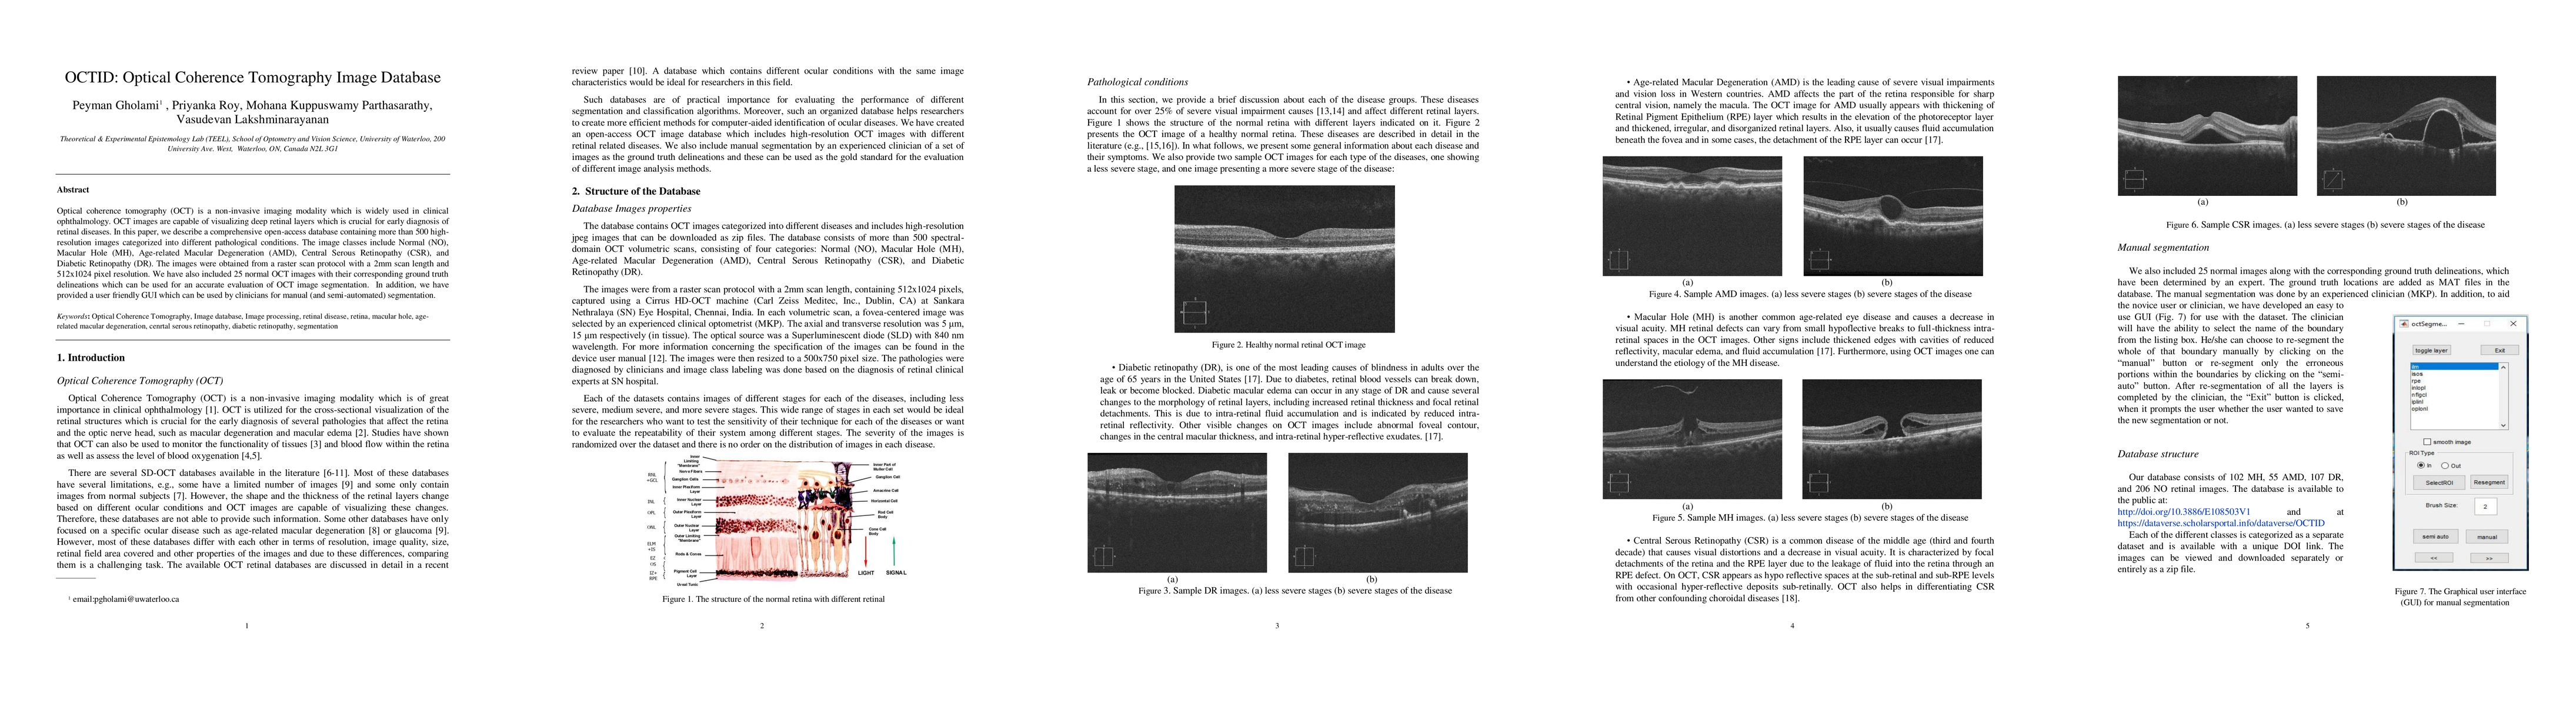

Optical coherence tomography (OCT) is a non-invasive imaging modality which is widely used in clinical ophthalmology. OCT images are capable of visualizing deep retinal layers which is crucial for early diagnosis of retinal diseases. In this paper, we describe a comprehensive open-access database containing more than 500 highresolution images categorized into different pathological conditions. The image classes include Normal (NO), Macular Hole (MH), Age-related Macular Degeneration (AMD), Central Serous Retinopathy (CSR), and Diabetic Retinopathy (DR). The images were obtained from a raster scan protocol with a 2mm scan length and 512x1024 pixel resolution. We have also included 25 normal OCT images with their corresponding ground truth delineations which can be used for an accurate evaluation of OCT image segmentation. In addition, we have provided a user-friendly GUI which can be used by clinicians for manual (and semi-automated) segmentation.

The OCTID database was created using a raster scan protocol with a 2mm scan length and 512x1024 pixel resolution.

• The database contains over 500 high-resolution images categorized into different pathological conditions.

• 25 normal OCT images were included with their corresponding ground truth delineations for accurate evaluation of OCT image segmentation.

• A user-friendly GUI was provided for manual and semi-automated segmentation.